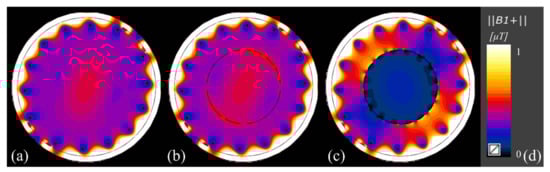

Figure 4 and Table 2 present the FDTD EM B 1 + simulation results. In case 1, the uniformity of the B 1 + map of the fat phantom in the ROI was 85.0%. In case 2, the uniformity of the B 1 + map of the fat phantom in the ROI using body coil transmission and reception with the 16-leg 13C PFT birdcage RF coil, containing the CPSCs, was 84.9%; the uniformity reduction between cases 1 and 2 was 0.10%. In case 3, the uniformity of the B 1 + map of the fat phantom in the ROI using body coil transmission and reception with the 16-leg 13C birdcage RF coil without CPSCs was 75.3%, indicating a significant uniformity reduction of 9.70% when compared to that in case 2.

In cases 1, 2, and 3, the average intensities of the B 1 + field of the fat phantom in the ROI were 0.417 μT, 0.415 μT, and 0.148 μT, respectively. Case 2 demonstrated an intensity reduction of 0.43% compared to case 1. However, case 3 demonstrated a significant intensity reduction of 64.5% when compared with case 1, as shown in Table 2.

Figure 4. Calculated B 1 + maps using Sim4Life. (a) B 1 + map of body coil with a uniform fat phantom without a 13C RF coil. (b) B 1 + map of body coil with uniform phantom with 16-leg PFT 13C birdcage RF coil containing CPSCs showing almost similar B 1 + map as (a). (c) B 1 + map of body coil with uniform phantom with 16-leg 13C birdcage RF coil without CPSCs showing degraded B 1 + map. The B 1 + fields in (ac) follow the color bar which is depicted in (d).